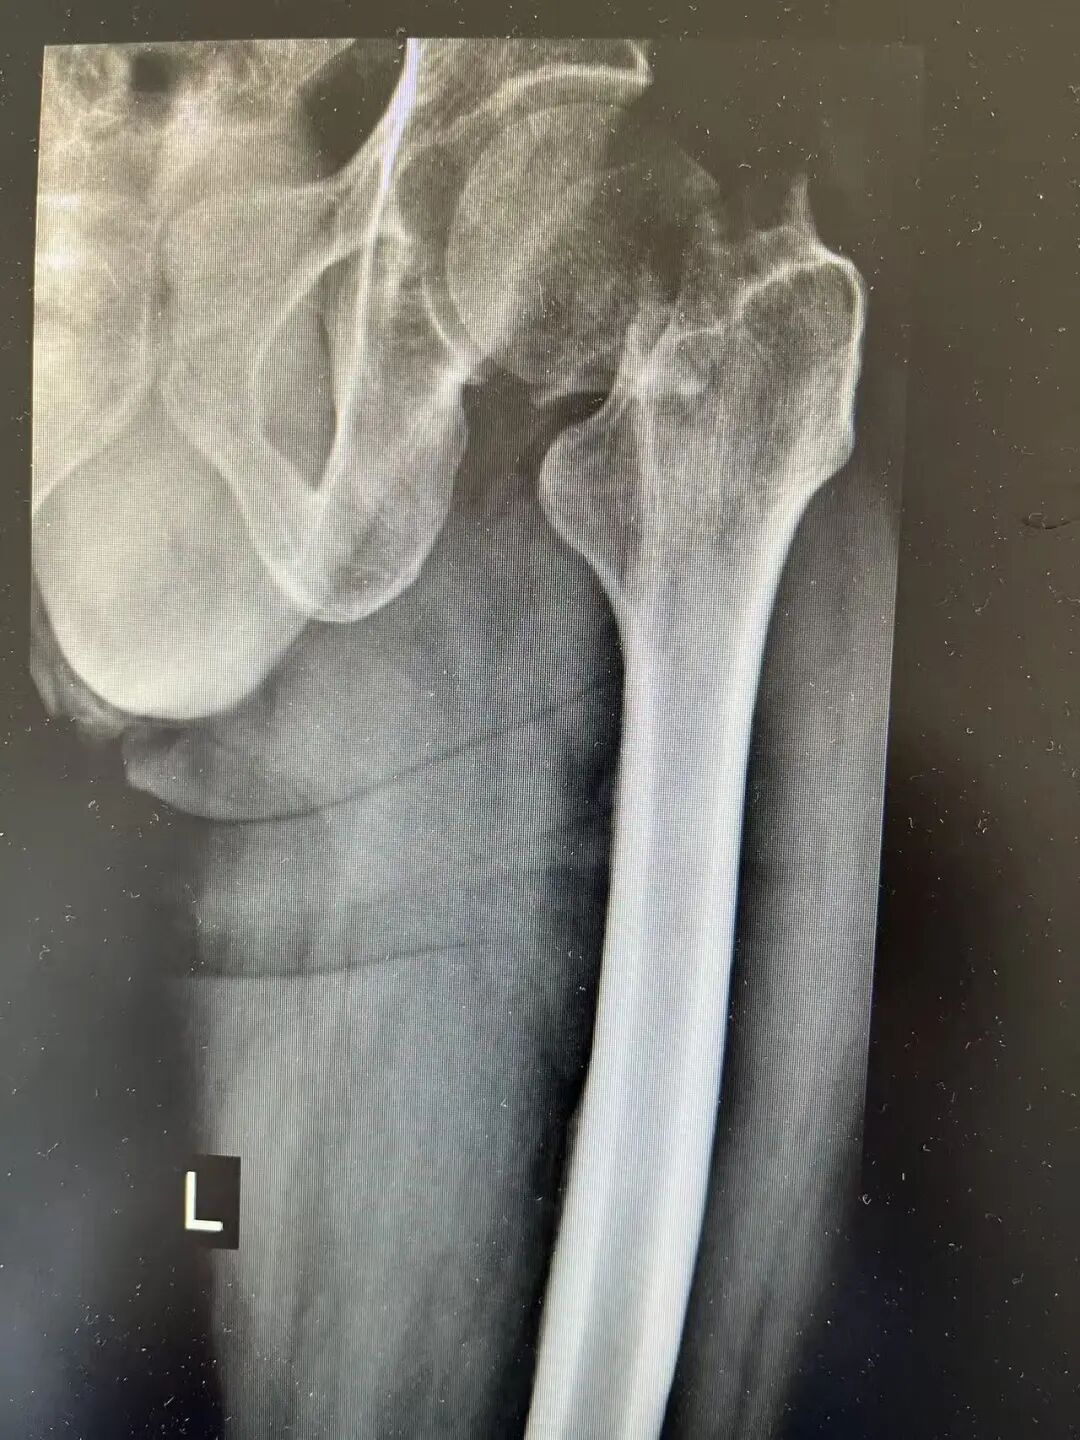

患者张先生(化名)因不慎摔倒致左髋部剧烈疼痛、活动受限,被紧急送入八医本部院区急诊医学部就诊,影像学检查明确诊断为“左侧股骨颈头下型骨折”,需手术治疗。然而,接诊团队很快发现,患者有长达二十余年每日大量饮酒史,存在明显酒精依赖症状。入院后不久,即出现震颤、焦虑、失眠、幻觉、躁动不安等典型酒精戒断反应,情况危急。

术前X线

“这类患者手术风险很高,”王金台主任医师指出,“酒精依赖不仅影响神经系统功能,还会导致肝功能异常、凝血障碍、心血管系统不稳定,且戒断期易诱发癫痫、谵妄,甚至危及生命。在这样的状态下进行手术,无异于在‘风暴中航行’。”同时,患者酒精依赖,如果行内固定治疗,术后对患者依从性要求很高,如患者不能配合,很可能造成内固定失效,且患者长期酗酒,股骨头坏死几率极高。结合患者实际情况并经多学科会诊(MDT)后,王金台主任团队决定为患者实施全髋关节置换术。